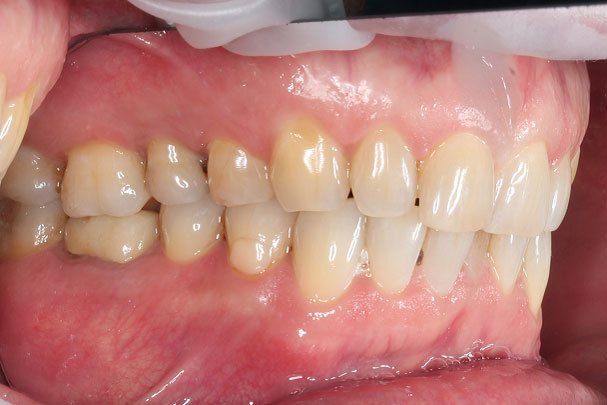

В ходе обследования было обнаружено отсутствие одного зуба и необходимость ортодонтического лечения с целью подготовки к имплантации и протезированию. Стоматолог-ортодонт выявил у пациентки скученность зубов верхней и нижней челюсти и повышенную стираемость зубов (бруксизм). Лечение было назначено на брекет-системе BIOQUICK. Перед ортодонтическими процедурами была проведена санация полости рта. Также на этапе ортодонтии наши врачи установили имплантат и приступили к этапу протезирования.

Было установлено 8 виниров в зоне улыбки: 4 винира на верхние и 4 винира на нижние зубы. Композитом мы восстановили клыковые ведения, установили коронку на имплантат 36 и коронки на зубы 45 и 46.